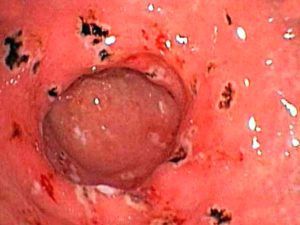

Ерозивнийгастрит - форма

Гастрит, особливо ерозивний, якщо до нього ставитися халатно, не лікувати, а заглушати содою, може привести в виразці шлунка і навіть прориву його стінок. Це захворювання небезпечно для життя.